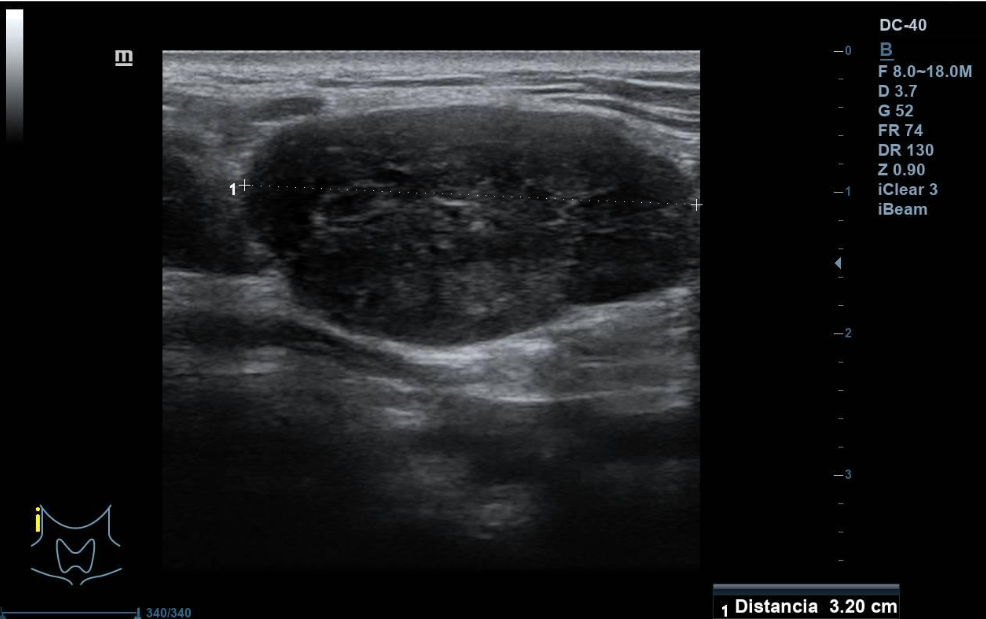

Se aprecian al menos dos lesiones intraparotídeas, una menor hipoecogénica, redondeada de unos 10 mm de diámetro máximo, doppler con vascularización mixta. La mayor de unos 3 cm de diámetro máximo, hipoecogénica, de contenido irregular, con áreas anecogénicas, de características sólidas, bien definido. Vascularización mixta, central y periférica. No se observan adenopatías cervicales de aspecto ecográfico patológico. La parótida contralateral, impresiona de normalidad.